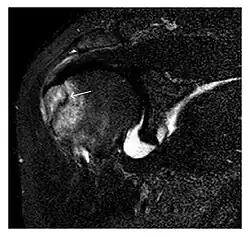

The greater tuberosity of the humerus is also an illustrative location of occult fractures. The osseous injury may follow seizures, glenohumeral dislocation, forced abduction, or direct impaction. They are commonly discovered on MRI in symptomatic patients with suspicion of rotator cuff tear. Coronal images are best suited for detection. They appear as crescentic oblique lines surrounded by a bone marrow edema pattern (Figure 5). The rotator cuff must be inspected since associated ligamentous lesions are common. In the ankle, malleoli and tarsal bones should be checked carefully for any cortical disruptions and radiolucent lines that may reveal a fracture. Awareness of the exact location of the pain will help direct the attention of the interpreter when searching for very subtle signs of fracture (Figure 6).[1]

- a

- b